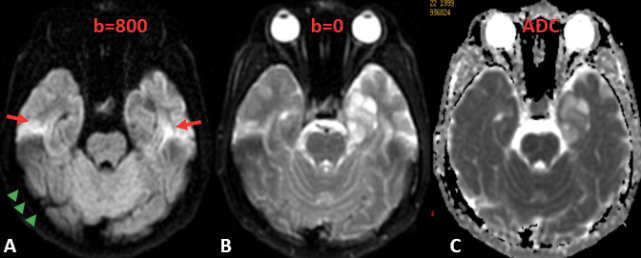

图片

图 4. A. DWI 上(b = 800)图像质量差且颅底有变形或磁敏感伪影的图像(红色箭),皮下脂肪为低信号(绿色箭头);B. b = 0 的图像可以认为相当于低配版的 T2WI(实际上相当于是 GRE 成像的 T2*WI);C. ADC 图:在看完 DWI 后需要看 ADC 低不低